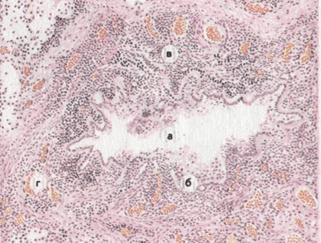

Рис. 10. Хронический гнойный бронхит с образованием бронхоэктазов.

а — просвет бронха неравномерно расширен; б — некроз и гнойное расплавление

слизистой оболочки; в — инфильтрация стенки бронха лейкоцитами;

г — склероз перибронхиальной ткани.